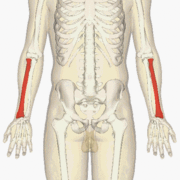

![]() The radius (shown in red) is a bone in the forearm. | |

The radius or radial bone is one of the two large bones of the forearm, the other being the ulna. It extends from the lateral side of the elbow to the thumb side of the wrist and runs parallel to the ulna, which exceeds it in length and size. It is a long bone, prism-shaped and slightly curved longitudinally.